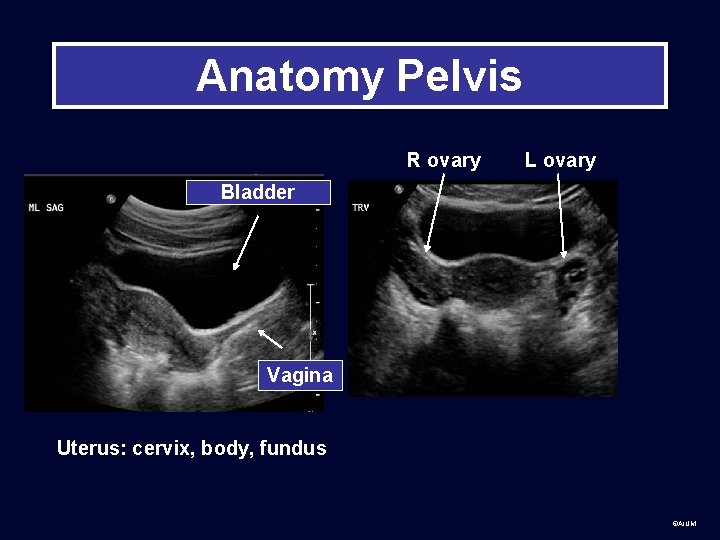

Anatomy Pelvis R ovary L ovary Bladder Vagina Uterus: cervix, body, fundus ©AIUM